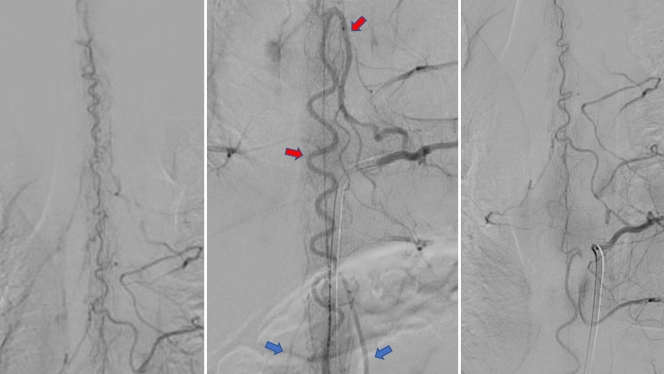

Les médecins découvrent alors ces images, qui montrent que ses artères y sont fortement déformées.

« Ses vaisseaux sont distendus, gonflés, tordus comme des spaghettis », explique Christine. En jargon médical, on parle d’un élargissement diffus, appelé ectasie, et d’une tortuosité des artères, avec une hyperhémie (un apport sanguin accru) et un œdème (gonflement) de la moelle épinière. Christine vulgarise : « Ses vaisseaux sanguins gonflent, dégonflent, et abîment sa moelle un peu plus chaque jour ».